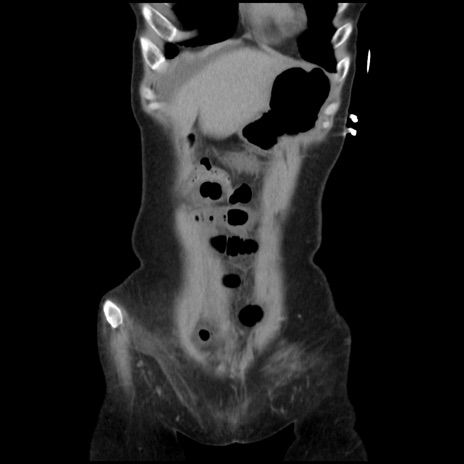

症例32(冠状断像)

【症例】40歳代 女性

【主訴】上腹部痛、嘔気・嘔吐

【現病歴】約9時間前頃から急に上腹部痛、嘔気、嘔吐が出現。改善しないため救急要請。

【既往歴】子宮頚癌(広汎子宮全摘術、放射線療法)、腸閉塞

【身体所見】腹部:平坦、軟、腸雑音亢進、上腹部を中心に腹部全体に圧痛あり。

【データ】WBC 8400、CRP 0.03